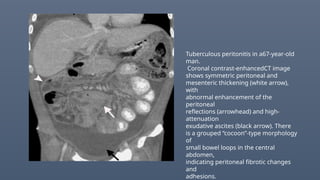

Tuberculous peritonitis in a67-year-old

man.

Coronal contrast-enhancedCT image

shows symmetric peritoneal and

mesenteric thickening (white arrow),

with

abnormal enhancement of the

peritoneal

reflections (arrowhead) and high-

attenuation

exudative ascites (black arrow). There

is a grouped “cocoon”-type morphology

of

small bowel loops in the central

abdomen,

indicating peritoneal fibrotic changes

and

adhesions.